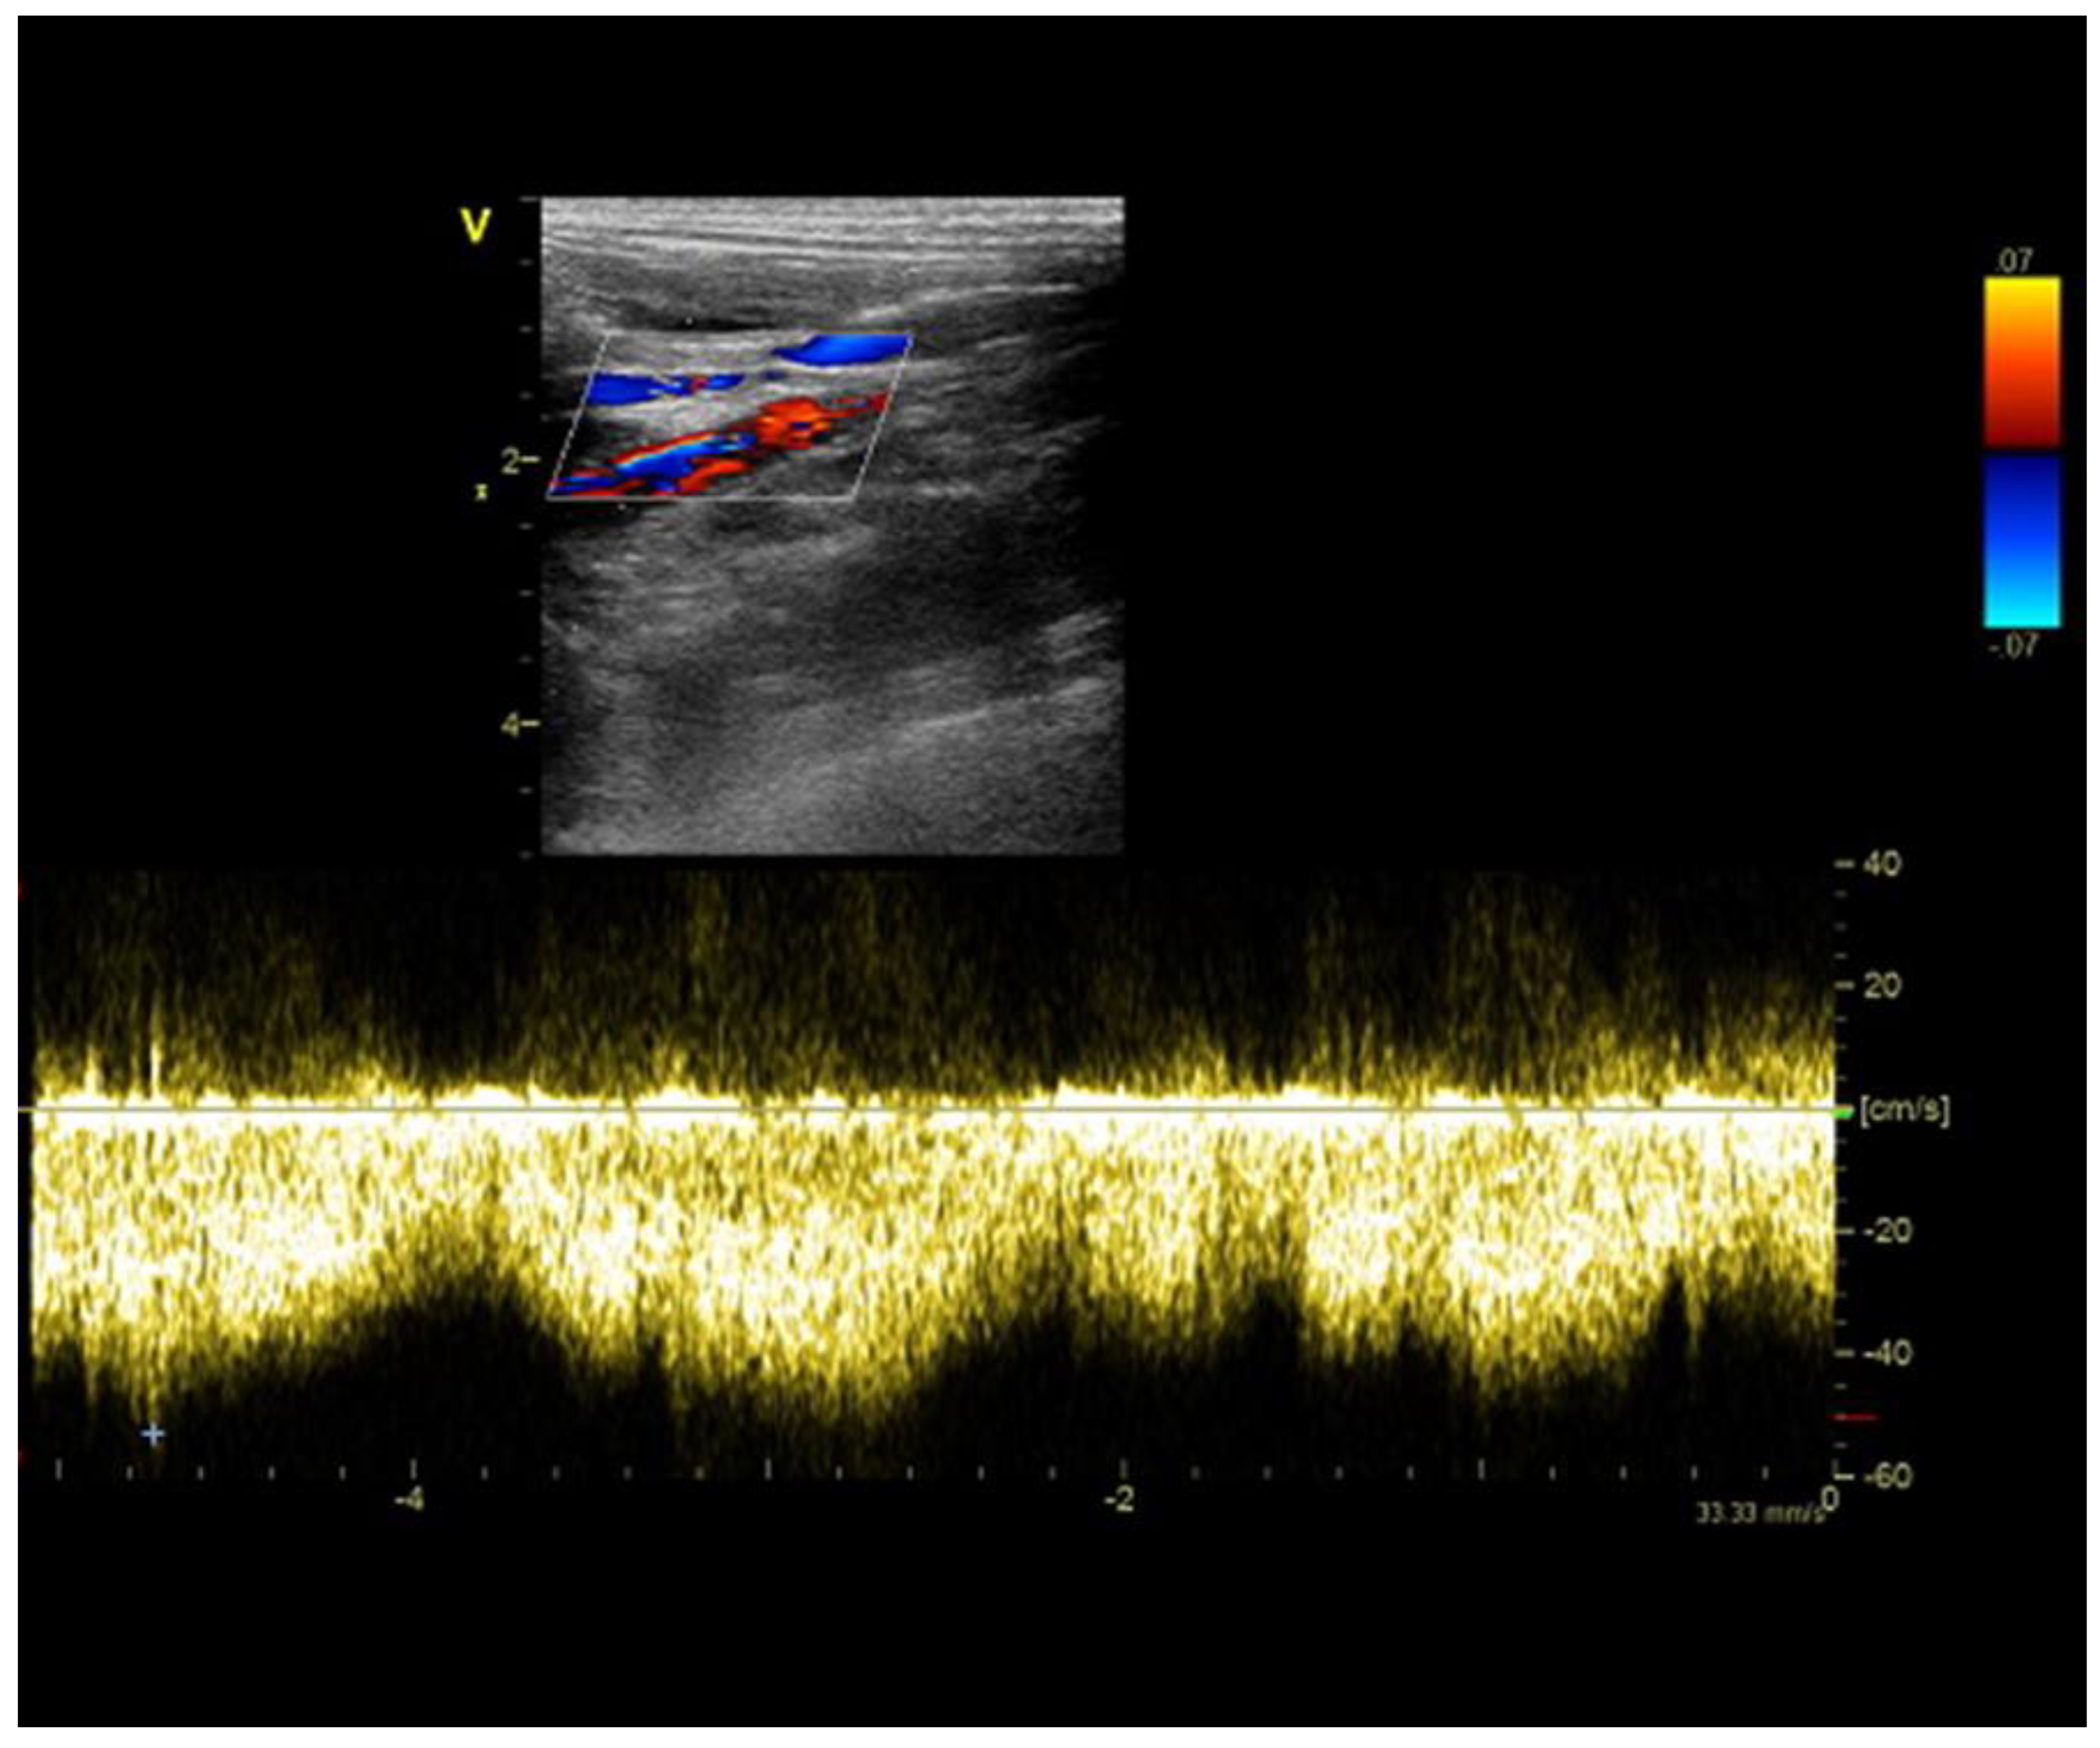

2.1. Case A (Human)

2.2. Case B (Human)

6.5. Portal Vein Blood Flow

6.6. Portal Vein Tributaries